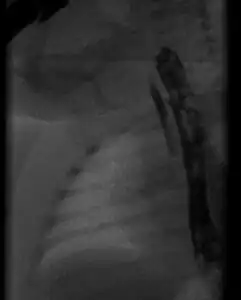

Radiograph with oral contrast showing h-type tracheoesophageal fistula in a newborn